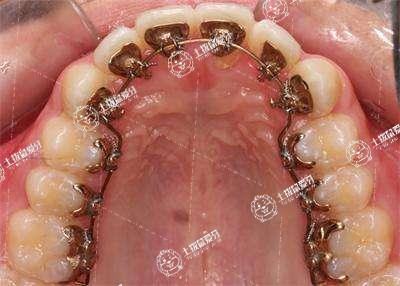

具體的價格可以根據(jù)口腔的健康狀況決定。如果是單純的矯正牙齒,通??梢耘宕麂摻z牙套進(jìn)行矯正,能夠使牙齒排列整齊,同時還可以提高咀嚼能力,通常需要兩年左右可以改善牙齒的狀況。若牙齒比較擁擠,在矯正過程中需要拔牙治療,治療的時間相對來說較長一些,收費的價格比較昂貴,可能需要20000元左右,甚至還有可能會更高,才能使牙齒排列整齊。

牙列不齊矯正價格大概需要5000元到10000元左右,要根據(jù)選擇的材料來進(jìn)行判定。在做矯正牙齒的時候選擇的是隱形牙套,可能舒適度和美觀度都會大大提高,效果會更加明顯,不會對牙齦組織造成摩擦,可能價格在10000元,如果選擇是鋼絲牙套,可能價格在5000元。矯正牙齒可以對牙齒施加壓力,讓牙齒慢慢的移動位置,可以有效地解決牙列不齊或者牙齒過度擁擠的狀態(tài),需要定期到醫(yī)院檢查。